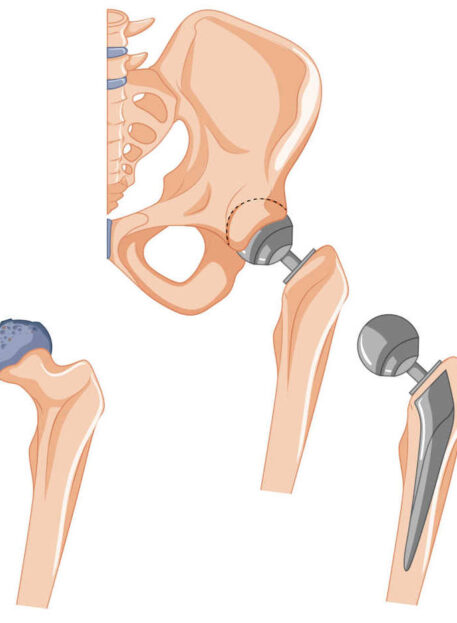

Totalna endoproteza KOLKA

TEP kolka (totalna endoproteza kolka) je operativni poseg, pri katerem se poškodovani ali obrabljeni kolčni sklep nadomesti z umetnim sklepom. Poseg je najpogosteje indiciran pri:

- napredovali artrozi kolka,

- hudih bolečinah v kolčnem sklepu,

- omejeni gibljivosti,

- neuspešnem konzervativnem zdravljenju,

- poškodbah kolka (zlomi, degenerativne spremembe).

Operacija sama po sebi še ne zagotavlja optimalnega izida – ustrezna in strokovno vodena rehabilitacija je ključna za dolgoročen uspeh.